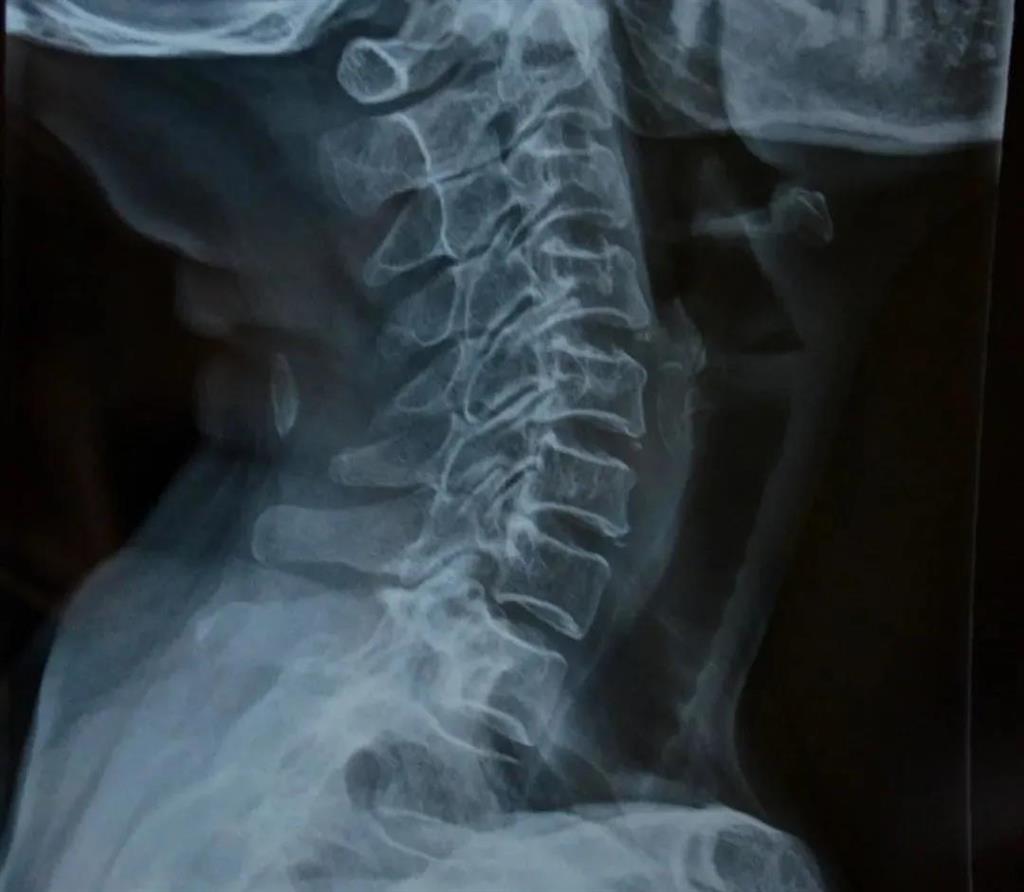

X光片檢查

頸椎X片是頸椎病的常規(guī)檢查方法,常表現(xiàn)為頸椎正常生理曲度消失或者是反張,椎間隙狹窄,椎管狹窄,椎體后緣骨贅形成,在頸椎的過伸過屈位片上還可以觀察到頸椎節(jié)段性不穩(wěn)定。

——圖源網(wǎng)絡(luò)

可得信息:

(1)判斷頸椎的大體形態(tài)、曲度、穩(wěn)定性;

(2)判斷骨頭結(jié)構(gòu)是否出現(xiàn)破壞的情況;

(3)是否出現(xiàn)骨質(zhì)增生或先天畸形的情況。